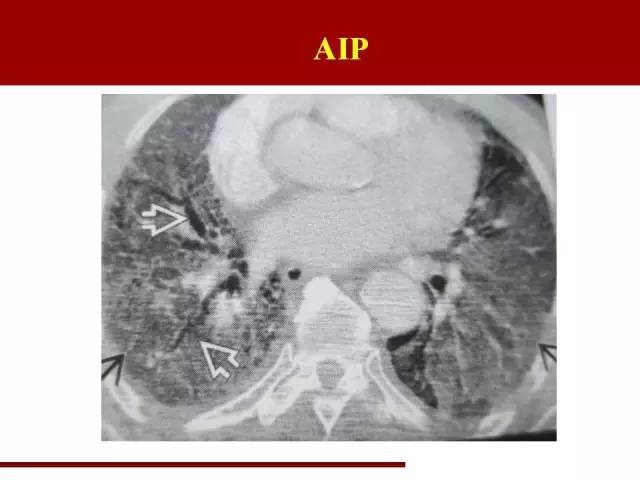

AIP一个特点:快

进展迅速是其特点

在原有的间质性肺炎的基础上迅速进展

这个诊断没有十足把握建议不要轻易下

因为下完之后就几乎判死刑,大部分病人在一个月内死亡